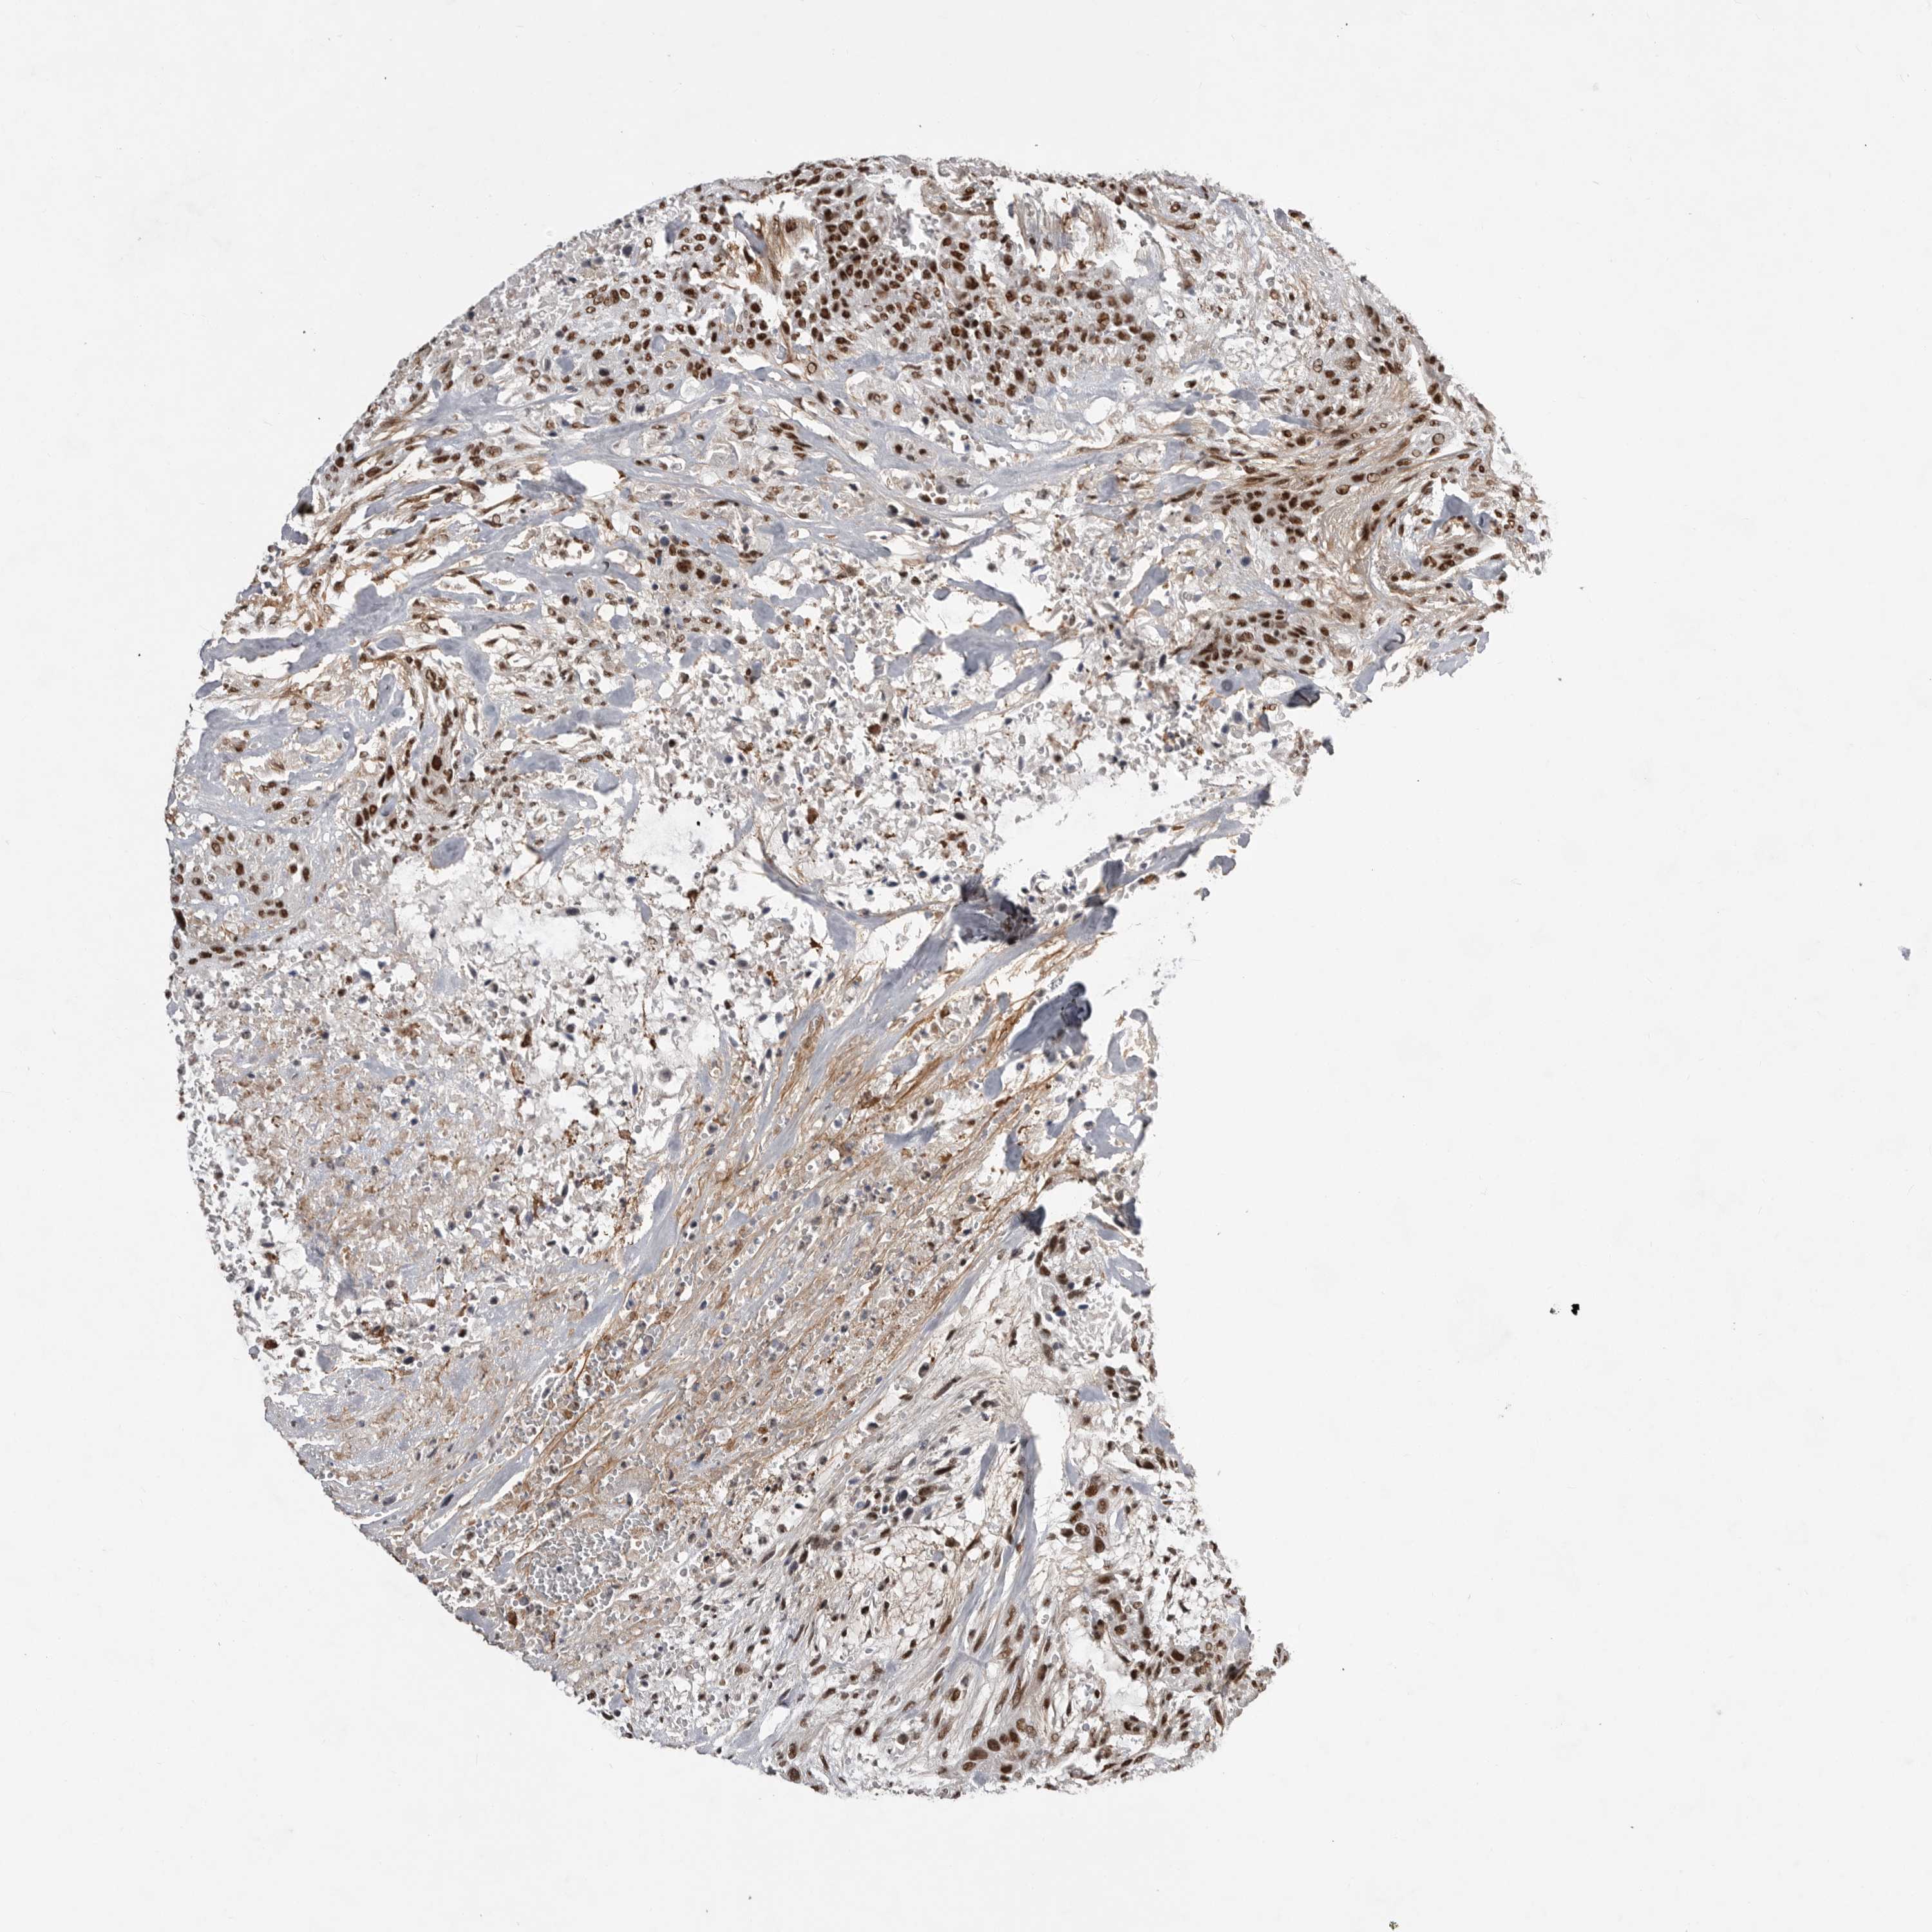

UROTHELIAL CANCER - Protein expressioni

A mouse-over function shows sample information and annotation data. Click on an image to view it in a full screen mode. Samples can be filtered based on level of antibody staining by selecting one or several of the following categories: high, medium, low and not detected. The assay and annotation is described here.

Note that samples used for immunohistochemistry by the Human Protein Atlas do not correspond to samples in the TCGA dataset.

Antibody stainingi

Antibody staining in the annotated cell types in the current human tissue is reported as not detected, low, medium, or high, based on conventional immunohistochemistry profiling in selected tissues. This score is based on the combination of the staining intensity and fraction of stained cells.

Each image is clickable and will lead to virtual microscopy that enables deeper exploration of all samples and also displays staining intensity scores, fraction scores and subcellular localization as well as patient and tissue information for each sample.

Antibody HPA027406

Antibody HPA027417

Antibody HPA027452

Staining

High

Medium

Low

Not detected

Intensity

Strong

Moderate

Weak

Negative

Quantity

>75%

75%-25%

<25%

None

Location

Nuclear

Cytoplasmic/membranous

Cytoplasmic/membranous,nuclear

Urothelial carcinoma, Low grade

Urothelial carcinoma, High grade